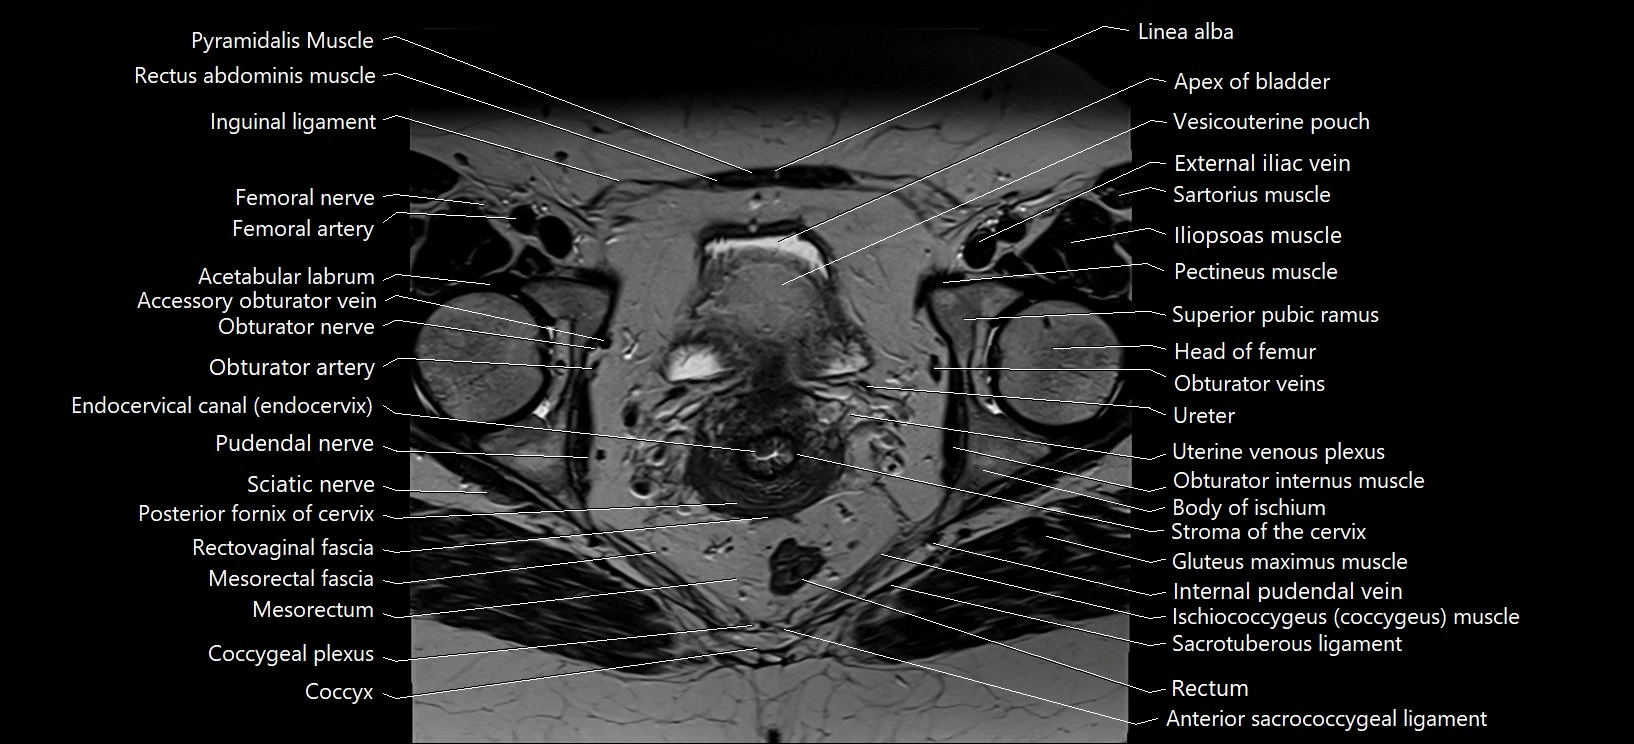

- Acetabular labrum

- Adductor brevis muscle

- Adductor longus muscle

- Apex of urinary bladder

- Body of ischium

- Body of urinary bladder

- Cervix of uterus

- Coccygeal plexus

- Coccyx

- Endocervical canal

- Femoral nerve

- Gluteus maximus muscle

- Gluteus medius muscle

- Head of femur

- Iliococcygeus muscle

- Iliopsoas muscle

- Inguinal ligament

- Internal pudendal vein

- Mesorectal fascia

- Mesorectum

- Obturator internus muscle

- Obturator nerve

- Obturator artery

- Obturator vein

- Pectineus muscle

- Posterior fornix of cervix

- Pubic symphysis

- Pubococcygeus muscle

- Puborectalis muscle

- Pudendal nerve

- Pyramidal muscle (pyramidalis muscle)

- Rectovaginal septum (rectovaginal fascia)

- Rectum

- Sartorius muscle

- Sciatic nerve

- Stroma of the cervix

- Superior pubic ramus